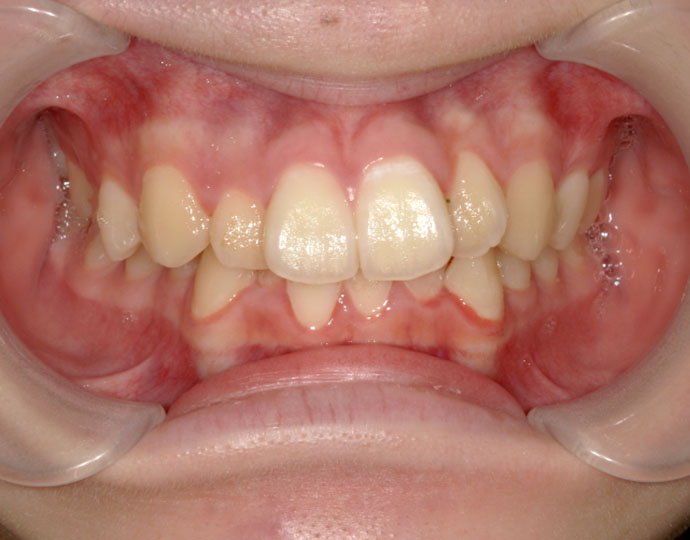

治療後

| 患者様 | 女性 18歳 |

| 主訴 | 歯並びを綺麗にしたい。 |

| 診断 | 叢生歯列不正咬合 |

| 治療方針 | 上下顎左右第一小臼歯の抜歯(計4歯) |

| 治療に使用した装置 | セルフライゲーションブラケット(インタラクティブタイプ) |

| 治療期間 | 2年2カ月 |

| 治療回数 | 24回 |

| 治療費(自費診療) | 847,000円(税込み) |